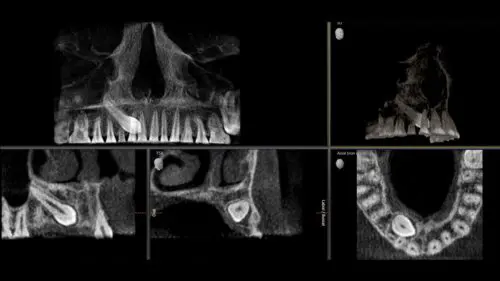

4 volumi per più Possibilità

Dimensioni del volume per tutte le esigenze, da Ø 5 x 5.5 cm a Ø 17 x 13 cm.

DCS – Nitidezza per dettagli precisi

Il sensore di conversione diretta (DCS) ha ridefinito lo standard della radiologia panoramica. I raggi X vengono convertiti direttamente in segnali elettrici – a differenza dei sistemi convenzionali, non vi sono perdite di segnale dovute alla conversione della luce. Ciò significa una migliore informazione sull’immagine. Il risultato sono immagini con un livello di nitidezza straordinariamente elevato, anche a dosi estremamente basse.

Utilizzando un sensore dedicato, ottieni p.a. laterale e simmetrico. o a.p. così come le immagini del carpo. Per i denti fuori sede, è anche possibile utilizzare i raggi X 3D per determinare la loro posizione esatta.